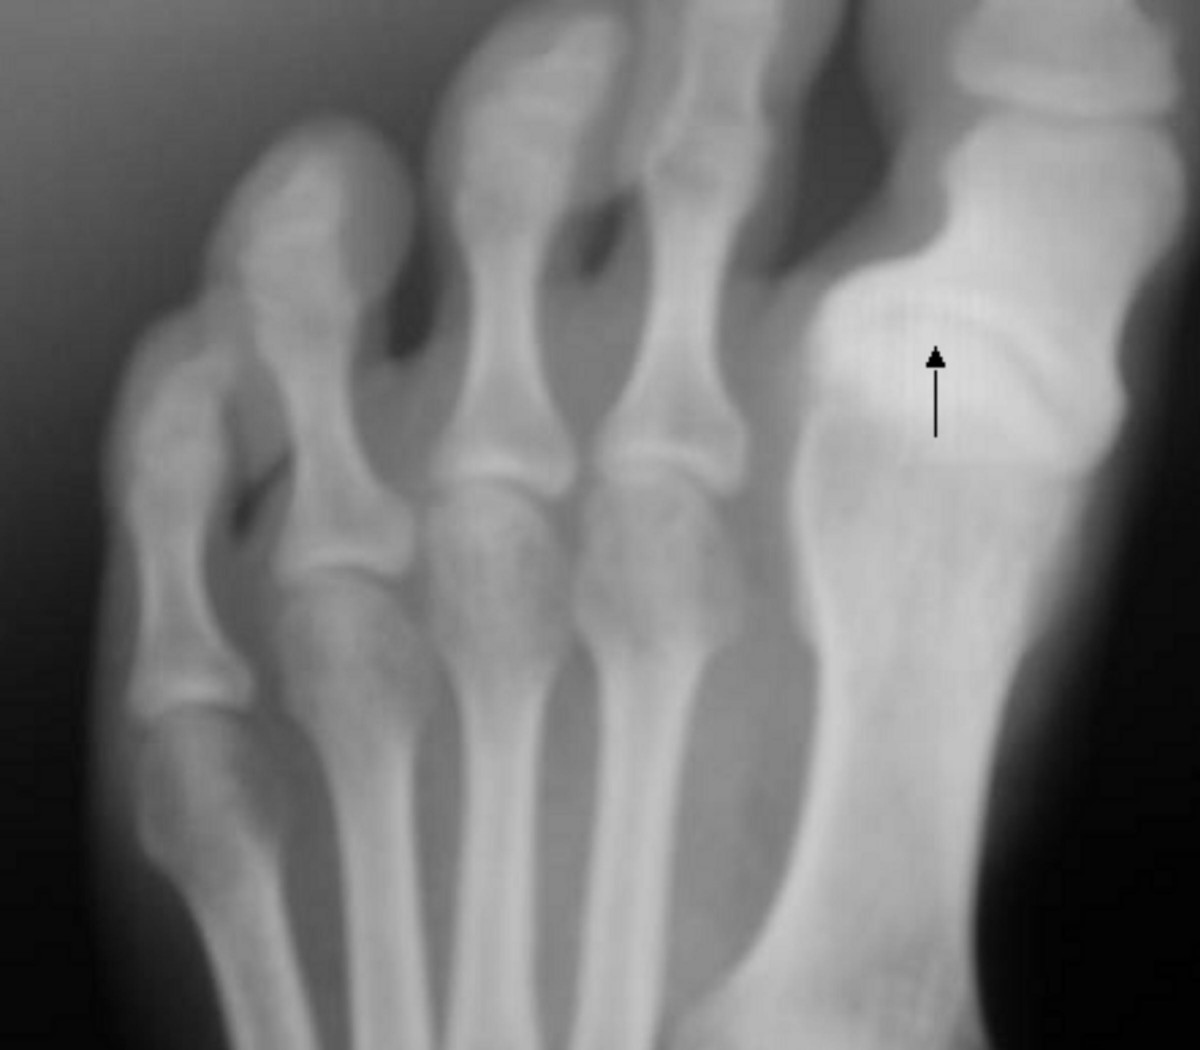

Sometimes, the swelling is related to inflammation. If your joints in your hands or feet are consistently swollen, stiff, and achy, it could point to arthritis. Rheumatoid arthritis often affects both sides of the body simultaneously, while gout famously causes a sudden, excruciatingly painful and swollen big toe. Even a simple overuse injury, like Achilles tendonitis from a new workout routine, can leave your ankles puffy and sore.